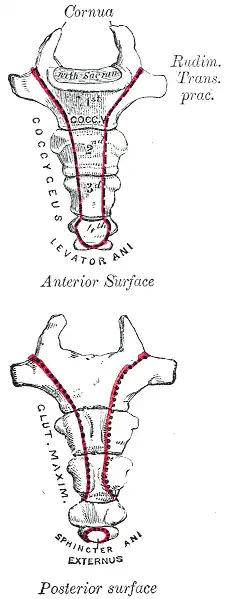

The coccyx is located at the base of the spine, under the sacrum. It is the last section of the ape vertebral column. Most commonly in humans it comprises 3 to 5 fused (or, more rarely, separate) vertebrae, and is approximately 4 to 10 cm in length. The coccyx is attached to the sacrum by a fibrocartilaginous joint, called the sacrococcygeal symphysis, allowing for some (but little) movement.